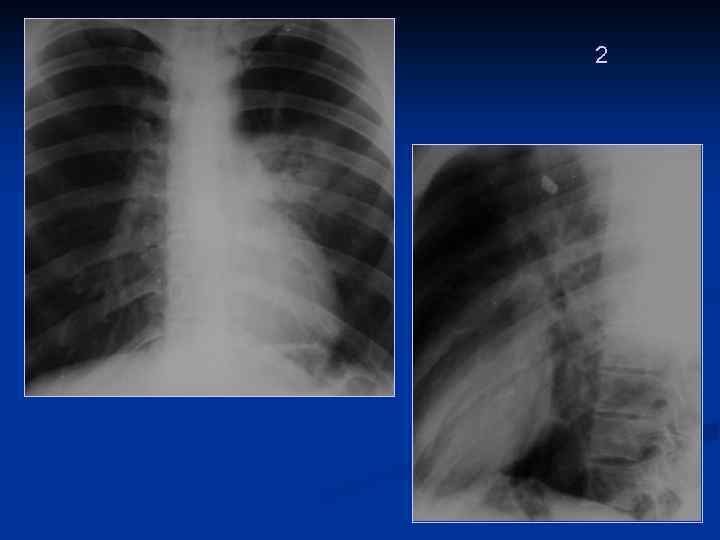

1 Пациентка 68 лет, поступила с СН Двусторонняя эастойная ндолевая ПН На этом фоне нельзя исключить ТЭЛА (жидкость, инфаркты)

2 Операция на ЖКТ (Cr recti), находится в реанимации Кровохарканье, боли в грудной клетке, лихорадка. Есть сопутствующая сердечно -сосудистая патология. После операции выявлены изменения в легких. Инфаркт -пневмония

Длительное течение пневмонии, отсутствие выраженной динамики 1

Через 10 дней

2